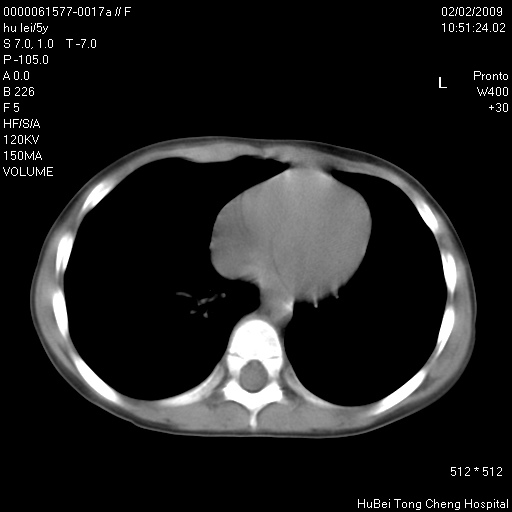

标题: PED1732:M5Y,右肺囊性占位!

患者:男,5。无明显不适,拍胸片考虑右肺囊肿。

行ct扫描,图象如下: